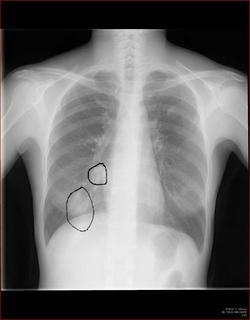

こちらを見て下さい。

わかりにくいかもしれませんが、このあたり。

気管が追いにくい、無くなっているようにも見えます。